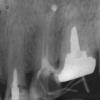

Serg1977 Опубликовано 15 августа, 2009 Поделиться Опубликовано 15 августа, 2009 (изменено) Здравствуйте уважаемые врачи и пациенты!Хочу получить прогноз по поводу возможности сохранения левой верхней шестерки, которая входит в мост 4-5-6 (все три зуба присутствуют).Итак по порядку. В 2004 году я "сбежал" из клиники после того, как корень запломбированного зуба воспалился на второй день после пломбировки (канал оказался пуст). ответ "врач отвлекся" меня не устроил и я нашел прекрасного специалиста благодаря сети интерент. Тройку зубов 4-5-6 ввиду сильного их разрушения новый врач порекомендовал протезировать мостом, вклеив в зубы культевые вкладки. я согласился с таким планом лечения.вот исходный снимок.видно что 4 и 6 залечены при помощи штифтов и разряжение около верхушки корня 5ки. сразу хочу обратить внимание что в 6ке корни запломбированы резорцин-формалиновой пастой в городской поликлинике много лет тому назад. не имея возможно перелечивания каналов 6ки врач расширил центральный канал и сделал культьевую вкладку из серебряно-паладиевого сплава. каналы 5ки были перелечены гуттаперчевыми штифтами, виден небольшой выход пасты в полость над верхушкой корня 5ки. четверка была залечена пастой, которую врач также заменил на гуттаперчуна снимке видны временные пломбы, с ними и вкладкой в 6ке я ходил неделю или две для подстраховки от воспаления. после чего в 4 и 5 были сделаны вкладки и вся тройка зубов была соединена в мост. прошло четыре с половиной года и 12 августа (кстати девятая годовщина гибели АПРК К141 "Курск") я почувствовал боль при накусывании на мост. Изначально я не предал этому значения, боль была почти незаметной. В ночь с 13го на 14е боль не дала мне спать ночью и с утра я поехал к врачу. выяснилось что принимать он будет только в понедельник 17го числа. Врач-терапевт осмотрела мост и сказала что держится он хорошо и есть болевые ощущения при постукивании по нему (самые сильные на 6ке). Порекомендовала ждать понедельника когда врач снимет мост и будет разбираться с проблемой из лекарств порекомендовала кетанов и сумамед. Но в ночь с 14е на 15е появился флюс напротив корней 6ки в мосту а в течении сегодняшнего 15го числа отек щеки. Боль почему-то прошла, даже перестал принимать кетанов , есть только давящее ощущение в щеке. Врача ждать еще более суток посему вопросы. 1. нет ничего опасного в таком ожидании? терпения-то у меня хватит, вопрос в сохранности зубов и здоровья. Если опасность есть, то куда бечь (адреса пароли явки в личку)? Живу я в ближнем подмосковье, набрать в гугле "стоматология" могу, но срочно выбрать врача..... 2. насколько велики шансы сохранить проблемную 6ку путем резекции верхушки корня или удаления одного из корней например. (а проблемы скорее всего с 6кой, кроме того 4ку и 5ку можно перепломбировать ибо в них гуттаперча, правда я не уверен что культевую вкладку можно удалить). Изменено 15 августа, 2009 пользователем Serg1977 Ссылка на комментарий

Doktor Max Опубликовано 20 августа, 2009 Поделиться Опубликовано 20 августа, 2009 желаете себе проблем - оставляйте зуб.гарантий,что каналы такого зуба перелечат,нет никаких.Проблемы на этой 6ке были и 4 года назад- воспаление на дистальном корне на сегодняшний день увеличилось до размеров как минимум кистогранулемы. при таком раскладе и до гайморита недалеко.А это уже гораздо серьезнее.так что удалите и живите спокойно. А хороший имплантант лучше плохого зуба. Ссылка на комментарий